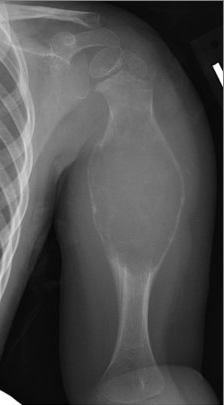

Radiograph of ABC in Humerus

Radiograph of a child's humerus (arm bone) with an aneurysmal bone cyst that shows expansion of the bone with a very thin outer bone cortex. An MRI can help confirm the diagnosis.

Reproduced from Lee DH, Hills, JM, Jordanov MI, Jaffe, KA: Common Tumors and Tumor-Like Lesions of the Shoulder. J Am Acad Orthop Surg 2019; 27(7):236-245.